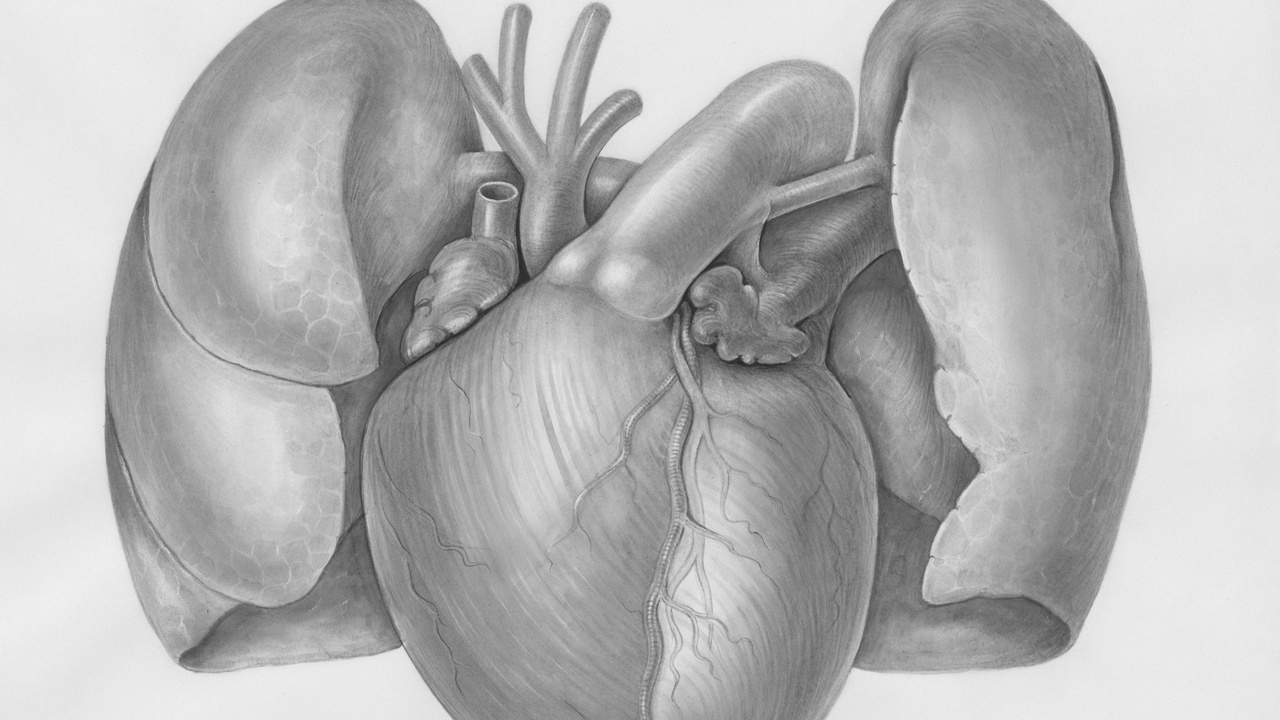

Anatomy and How the Lungs Work

The lungs are built for two complementary jobs: maximize the surface for gas exchange, and keep that surface clean and well perfused. Below you’ll find three related themes: the alveolar surface area that enables rapid oxygen uptake; the mucociliary clearance system that removes particles and microbes; and the lung’s specialized blood supply that makes diffusion extremely efficient. These basics set the stage for the numbered facts that follow.

3. Lungs have a specialized blood supply that maximizes gas exchange

Blood reaches the lungs through two systems: the pulmonary arteries carry deoxygenated blood from the right ventricle to the alveolar capillaries for gas exchange, while the bronchial circulation supplies airway tissues with nutrients.

The pulmonary capillary network is extremely dense, minimizing the distance oxygen must diffuse into blood. That geometry is why even small changes—fluid in the alveoli (pulmonary edema) or blocked vessels (pulmonary embolism)—can sharply reduce oxygen uptake.